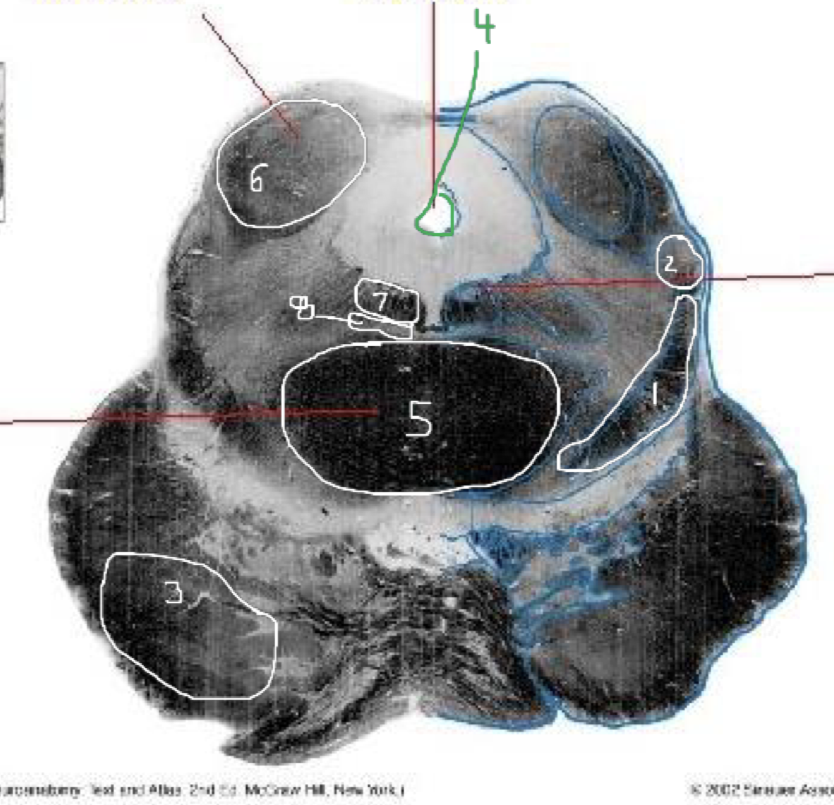

1

Medial Lemniscus - Rostral Pons

2

Spinothalamic Tract - Rostral Pons

3

CST - Rostral Pons

4

Cerebral Aqueduct - Rostral Pons

5

Middle Cerebellar Peduncle - Rostral Pons

6

Superior Cerebellar Peduncle - Rostral Pons

7

Medial Longitudinal Fasciculus (MLF) - Rostral Pons